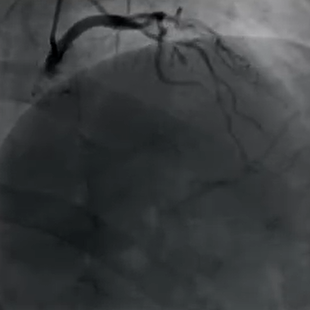

Case 1:高龄患者,左主干前四叉病变,前降支狭窄程度较重,血流TIMI2级,同时中间支也存在明显狭窄。由于前降支和回旋支角度较大,先扩张中间支,对前降支进行预扩张,之后前降支植入DES。由于中间支血流再次受限, rewire操作后行预处理,植入2.5*20mm的DCB,术后造影结果满意。

(Case 1术前)